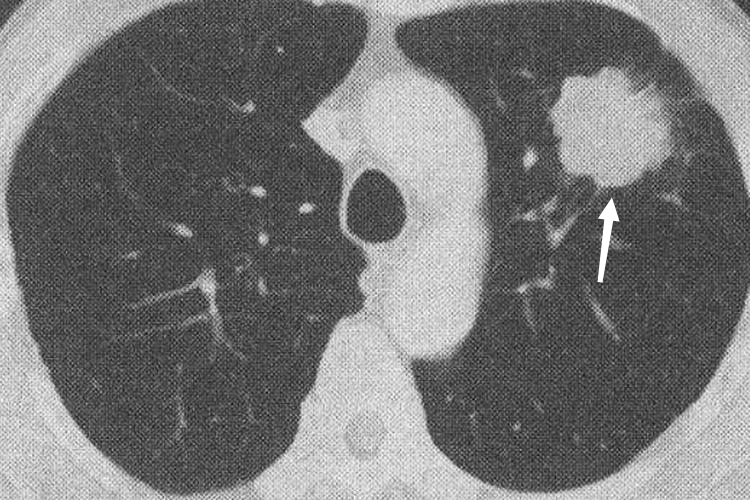

周围型:周围型肺癌CT可表现为磨玻璃结节或实性结节。